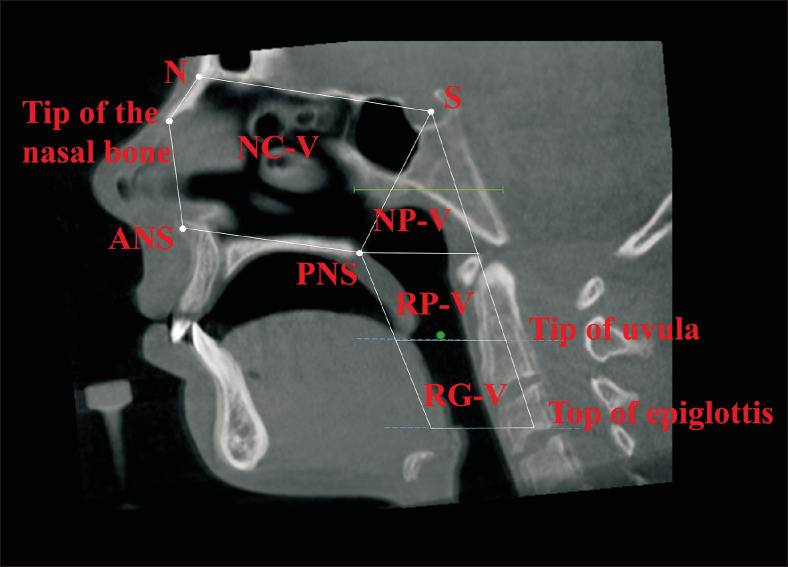

Methods: Pretreatment and post-expansion cone beam computed tomography scans of 30 patients (mean age: 18.6 years), diagnosed with maxillary transverse deficiency, were grouped into three (n = 10 each) according to expansion protocol: 1) MARPE; 2) SARME without PD [SARME-PD(-)]; 3) SARME with PD [SARME-PD(+)]. In NemoStudio software, eleven linear measurements were used to evaluate nasal and maxillary skeletal parameters. Eight airway measurements were used to evaluate the volume and minimum cross-section of the nasal cavity, nasopharynx, retropalatal region, and retroglossal region. Intragroup and intergroup changes were evaluated for statistical significance at P < 0.05.

Results: Nasal lateral, nasal floor, external maxillary, palatal, and maxillary intermolar widths significantly increased in all groups. In MARPE, nasal cavity and nasopharynx volumes and minimum cross-sectional area increased significantly. Nasopharyngeal volume increased significantly in SARME-PD(-), whereas nasal cavity volume and minimum cross-sectional area decreased significantly in SARME-PD(+). MARPE group showed greater expansion in nasal lateral width than SARME-PD(-) and SARME-PD(+) groups. Mean changes in nasal cavity volume, minimum cross-sectional area, and nasopharyngeal volume were significantly greater in MARPE than in SARME-PD(+).